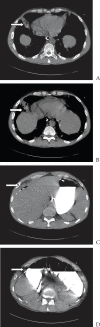

Figure 2

CT enterography. Colobronchial fistula tract (arrows) coursing from hepatic flexure and extending on the liver anteriorly and eventually communicating to right lower lobe bronchus with surrounding lung consolidation. Figures A and B demonstrate gastrointestinal contrast in the lung parenchyma. Figures C and D show fistula tract containing contrast from colon over the right lobe of the liver